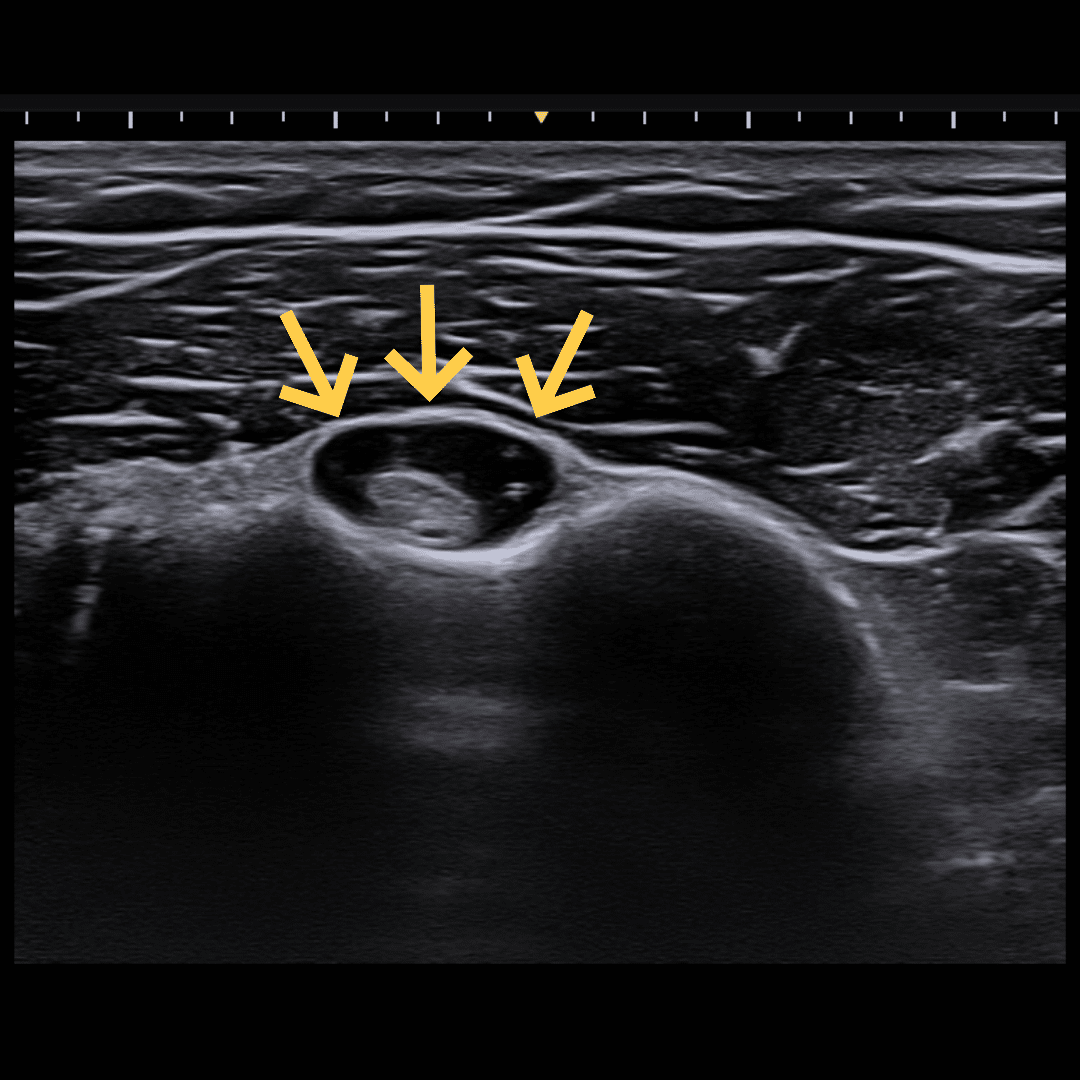

장기간에 걸쳐 힘줄의 구조적 변성이 일어난 만성 상태입니다. 힘줄 곳곳에 미세 파열이나 변성된 조직(구멍)이 존재합니다. 노년층이나 오랜 기간 운동을 해온 분들에게 흔합니다.

핵심 목표: “도넛의 구멍이 아닌, 도넛 자체를 치료하라”

이미 변성되어 죽은 조직(구멍, Hole)은 회복이 어렵습니다. 치료의 목표는 주변에 남아있는 건강한 힘줄 조직(도넛, Donut)을 강화하여 기능을 보상하게 하고, 통증을 유발하는 신경과 혈관을 차단하는 것입니다.

- 콜라겐 주사: 결손된 부위를 채워주어 치유를 돕는 지지체 역할을 합니다. 제 경험 상 비어있는 힘줄을 채우는데 가장 좋으며 다른 재생 치료의 기반이 되는 치료입니다.